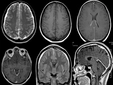

Hidrosefali tedavi edilmezse, beyin omurilik sıvısının (BOS) birikmesi nedeniyle beyin dokusunda baskı oluşur ve bu durum çeşitli komplikasyonlara yol açabilir. Uzun vadede, hidrosefali ciddi nörolojik sorunlara neden olabilir. Bunlar arasında motor fonksiyon bozuklukları, yürüyüş problemleri, denge kaybı, görme ve işitme sorunları, bilişsel gerileme ve hafıza kaybı sayılabilir. Ayrıca, hastanın yaşam kalitesi önemli ölçüde düşebilir; günlük aktivitelerini yerine getirme yeteneğinde azalma, sürekli baş ağrıları, bulantı ve yorgunluk gibi belirtiler ortaya çıkabilir.